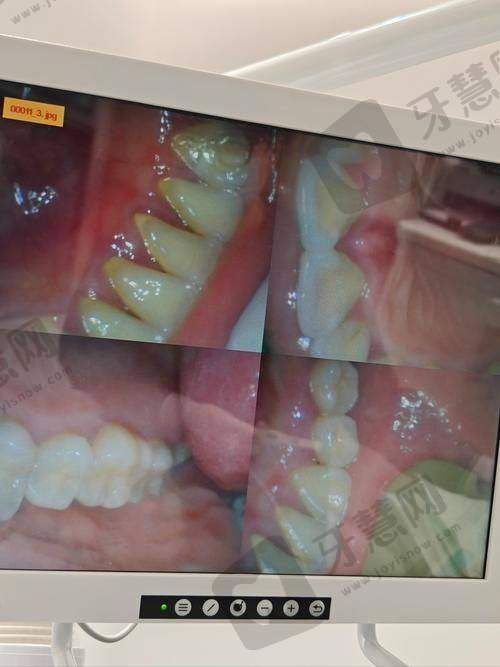

大连爱齿口腔门诊部(金域华府店)成立于2018年06月14日,是一家正规的口腔医疗机构,属于爱齿(大连)医疗企业管理旗下企业。该门诊部为患者提供全方面的口腔诊疗项目,包括常见的牙齿修复、正畸、美白等。在技术上,不断引进精良的口腔治疗技术,确保为患者提供效率高、安心的治疗方案。诊疗环境舒适宜人,设备精良齐全,为患者营造了良好的就医体验。门诊部企业规模为微型,员工人数10人(2024年),虽然规模不大,但医生们技术不错,经验多,能够根据患者的具体情况制定个性化的治疗方案。在当地,该门诊部凭借良好的服务和专精的技术,赢得了患者的广泛好评。

2. 精良的牙齿修复技术:采用精良的材料和技术进行牙齿修复,修复后的牙齿在外观和功能上都能与自然牙齿相媲美,且具有较高的耐用性。